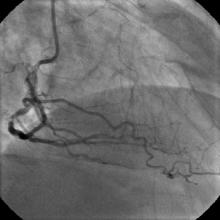

3) LAD: Ostial CTO ( Figure 2) with collaterals from RCA and LCX (Figure 3).

The left system was engaged with XB 3.5 guiding catheter through the femoral route. With the help of a 1.1x1.5mm CTO balloon, we directed a Shinobi guidewire towards the ostial LAD lesion (Figure 4). After making sure that the guidewire was pointing towards the CTO with its tip at the CTO lesion, we used the torquer to gently twirl the guidewire without forcing or overly manipulating it and allowed the guidewire to find its own way through the CTO by patiently twirling it at the lesion site. Within a few minutes, the guidewire jumped through the CTO lesion (Figure 5) and then through the lesion with the help of the CTO balloon (Figure 6). The path was first confirmed by engaging the RCA from the radial approach and injecting dye into the RCA (Figure 7). The CTO was then predilated with a 2.0x30mm Sapphire balloon (Figure 8 and Figure 9) and stented it with a 3.0x36mm DES (Figure 10 and Figure 11). Later the RCA was engaged with a JR 3.5 guiding catheter. A Cougar guidewire crossed the RCA lesion that was directly stented with a 3.0x13mm BMS (Figure 12 and Figure 13).